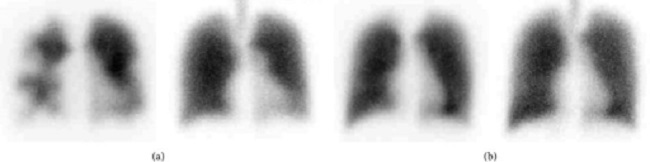

Ventilation-perfusion lung scan (V/Q scan) atau lung scintigraphy adalah pemeriksaan untuk skrining emboli paru. V/Q scan dapat memberikan gambaran perfusi pembuluh darah paru dan juga ventilasi kedua paru. Prosedur V/Q scan umumnya dilakukan selama 1 jam dan terdiri atas dua pemeriksaan, yaitu skintigrafi ventilasi dan perfusi.[1-3]

Umumnya, skintigrafi ventilasi dilakukan terlebih dahulu dengan pilihan radiotracer sesuai ketersediaan atau protokol masing-masing fasilitas kesehatan, misalnya Tc-99m, Xenon-133 (Xe-133), Xenon-127 (Xe-127), atau Krypton-81m (Kr-81m). Setelah itu, pemeriksaan dilanjutkan dengan skintigrafi perfusi menggunakan radiotracer 99mTc macro aggregated albumin (Tc-99m MMA). Hasil akan diinterpretasikan bersama untuk menilai probabilitas emboli paru.[1,4]

Pencitraan dengan planar atau single-photon emission computed tomography (SPECT) dapat dilakukan pada kedua pemeriksaan tersebut sesuai pilihan radiotracer. Setelah pemeriksaan, pasien dievaluasi untuk komplikasi tindakan yang mungkin muncul seperti reaksi alergi atau reaksi pada lokasi injeksi.[3,5]